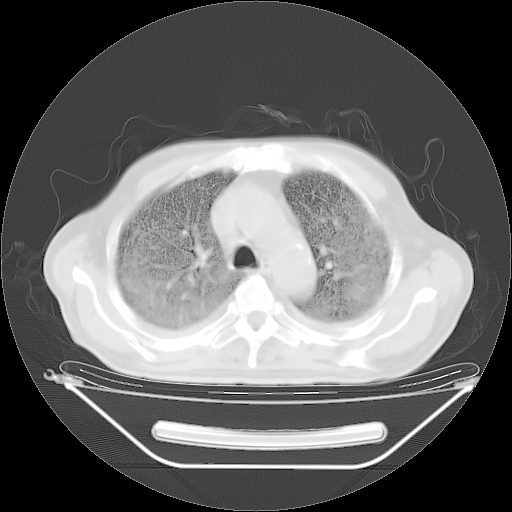

今天复查肺部CT,发现双肺广泛磨玻璃样改变。所以我把3月19日和5月9日相隔50天的肺部CT上传。请大家会诊。

2009年3月19日肺部CT片。

5月9日肺部CT(在4月27日齐鲁医院肺部CT描述部分肺组织磨玻璃样改变,12天后肺组织广泛磨玻璃样改变)